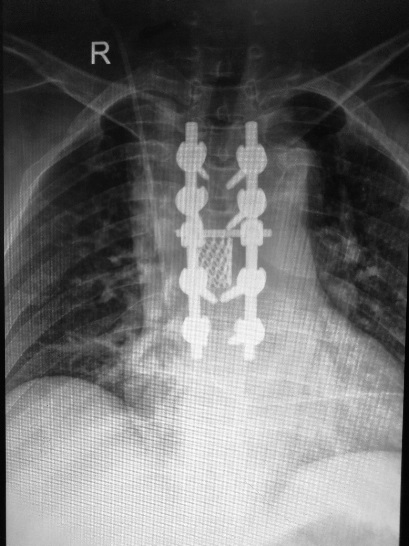

近期我科收治2名脊柱轉(zhuǎn)移性腫瘤的患者。2位女性患者突發(fā)胸背部疼痛及進(jìn)行性下肢無力,輾轉(zhuǎn)全國多家醫(yī)院,最終診斷為脊柱轉(zhuǎn)移性腫瘤。因腫瘤侵入椎管,治療難度高,遲遲未得到手術(shù)治療。經(jīng)人介紹來我院就診,為解除患者痛苦,主管醫(yī)生裴海波對病人詳細(xì)查體及全方位檢查后匯報(bào)張富軍主任,經(jīng)科室討論后,為患者制定了周密的手術(shù)方案—全脊椎整塊切除術(shù),并順利實(shí)施。

“全脊椎整塊切除術(shù)”這項(xiàng)技術(shù)由Tomita等于1994年提出,是一種脊柱腫瘤廣泛切除技術(shù),該技術(shù)通過將兩側(cè)椎弓根截?cái)?,然后于病椎上下方分別離斷椎間盤,將脊柱分為后方附件和前方椎體整塊取出。這項(xiàng)技術(shù)優(yōu)點(diǎn)是后路單一入路,有效防止腫瘤細(xì)胞擴(kuò)散,減少復(fù)發(fā)率。把腫瘤播散的風(fēng)險(xiǎn)降到最低。但該項(xiàng)手術(shù)技術(shù)需圍繞脊髓360°減壓,并且前側(cè)貼近肺組織并有主動(dòng)脈,稍有不慎易造成胸膜損傷、脊髓損傷、大血管損傷等,手術(shù)操作極其復(fù)雜,出血量大,手術(shù)時(shí)間長,技術(shù)難度高。該技術(shù)2006年國內(nèi)首例報(bào)道,目前陜西能完成此類手術(shù)的醫(yī)院也屈指可數(shù)。

我院骨科在張富軍主任帶領(lǐng)下,李靖教授的指導(dǎo)下,分別于2017年9月1日和2017年9月29日順利為2位患者行全脊椎整塊切除手術(shù)。手術(shù)平均時(shí)間3個(gè)半小時(shí),手術(shù)過程順利,均按照術(shù)前計(jì)劃成功將椎體整塊切除,未出現(xiàn)手術(shù)并發(fā)癥,術(shù)后恢復(fù)良好。